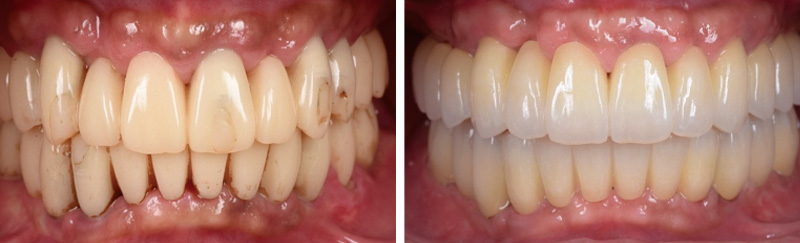

![[写真] 写真左:プロビジョナルレストレーションをステージごとに装着し、審美性や清掃性を意識した形態を模索 写真右:2022年プロビジョナルレストレーションの形態を踏襲し、最終補綴を装着](/academic/dentalmagazine/wp-content/uploads/sites/2/2026/04//196-12_photo04.jpg)

症例1-4 写真左:プロビジョナルレストレーションをステージごとに装着し、審美性や清掃性を意識した形態を模索。写真右:2022年プロビジョナルレストレーションの形態を踏襲し、最終補綴を装着。 -